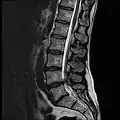

MRI

-

MRI lumbar spine with degeneration (sagittal T2 FRFSE) -

MRI lumbar spine with degeneration (sagittal T1 FSE) -

MRI lumbar spine with degeneration (sagittal FAST STIR) -

MRI lumbar spine pre-hemilaminectomy (sagittal T2 FRFSE)